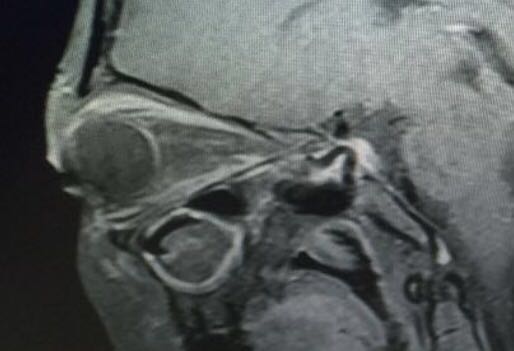

我们先以两张图片看看CT和磁共振分别能看到什么?

核磁共振

粗大的眼上直肌可清晰显示, 图像 美美哒!